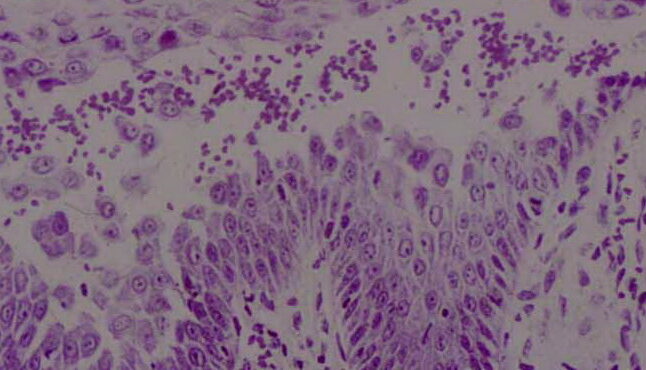

Read MoreHypertrophic actinic keratosis = التقران الضيائي الضخامي